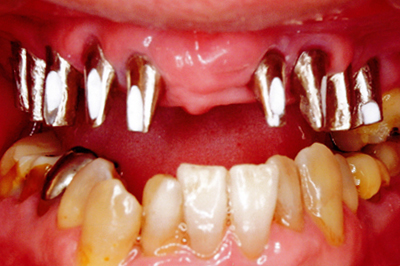

治療例2

歯ぐきが安定した状態

土台をたてた

噛める機能を回復

| ご費用 | 手術費用人工歯根 1本275,000円(税込) 上部構造 88,000円~110,000円(税込) |

|---|---|

| リスク・副作用 | 保険非適応(自費診療) 特定の全身疾患や持病のある方、顎骨密度の足りない方、妊娠中の方は手術ができない場合があります。 下顎のインプラント手術の際、偶発症のリスクがあります。 人工歯根が顎骨と癒着しないリスクがあります。 インプラント周囲炎になるリスクがあります。 |